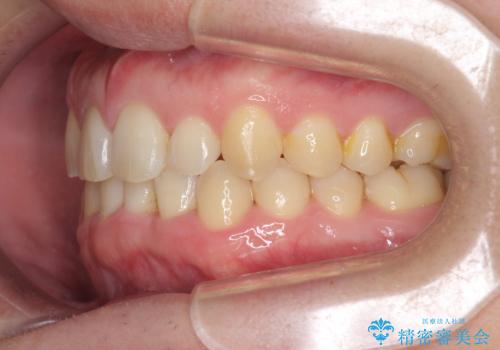

前歯のすき間 歯のがたつき

- 前歯のすき間とがたつきを主訴に来院。

右上の前歯は過去にがたつきがあったとのことで抜いてしまっていました。

歯の数を合わせるために、下の歯を1本抜いて矯正しています。

下の前歯を抜歯したことでブラックトライアングルができましたが、仕上げにIPRを加えることで目立たなくすることができました。